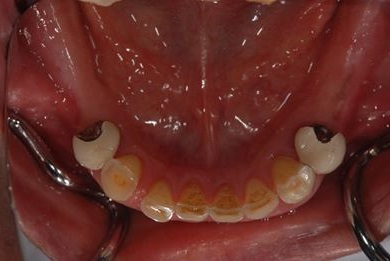

インプラントの症例写真 IMPLANT

骨再生スピードインプラント治療+セラミック治療

| 治療方針 | 上前歯部は、抜歯と同時にインプラントを埋入し、治療期間を短縮する。左上奥は、ソケットリフトにて上顎洞を拳上し、インプラント治療を可能にする。 | ||||||||||||||||||||||||||||||||

| 治療内容 | インプラント4本(ソケットリフト・抜歯即日)、テンポラリーインプラント2本、メタルボンドクラウン9本 | ||||||||||||||||||||||||||||||||